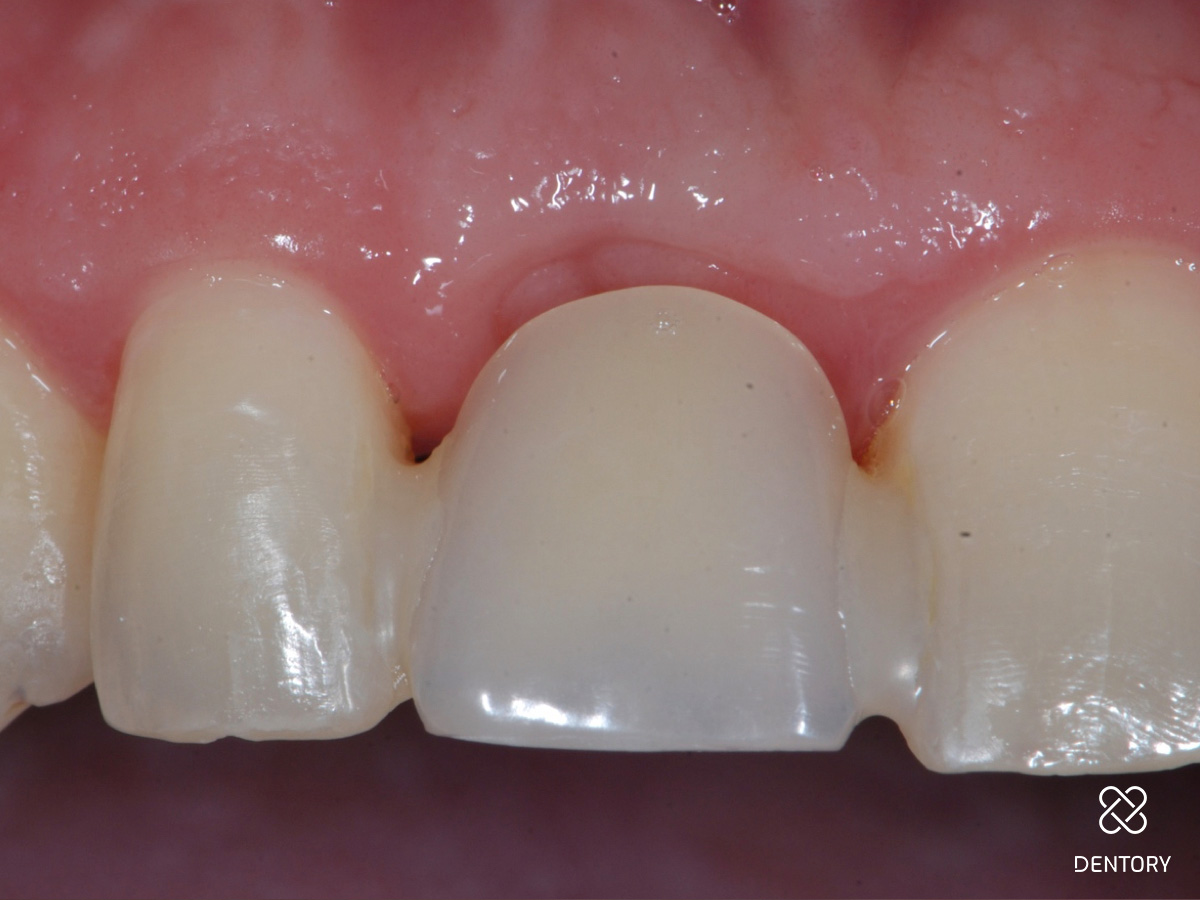

Abbildung 16

Heilung: Acht Wochen nach dem operativen Eingriff. Das Gingivatransplantat ist vollständig integriert. Die Gewebekontur konnte gut erhalten werden.

Abbildung 17

Heilung: 8 Wochen Post-OP - frontale Ansicht